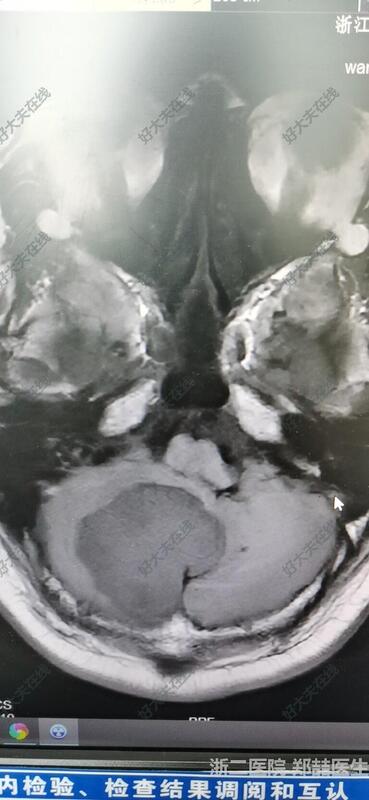

71岁男性,头晕1个月,行走不稳,伴恶心呕吐。头磁共振检查发现后颅窝占位。我院报告淋巴瘤或髓母细胞瘤。个人考虑脑膜瘤可能大,基底广泛。

后正中入路,切除肿瘤,基底广泛,冰冻考虑脑膜瘤。

患者恢复良好,可下地活动,头晕好转,无其他不适。头磁共振复查提示肿瘤全切。